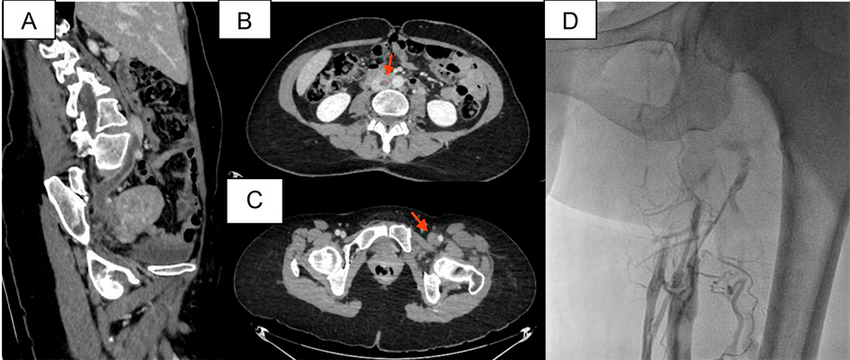

Presentamos el caso de una mujer de 49 años, con antecedente de diabetes tipo I, 3 gestas y 3 partos, uso de anticonceptivos en parche y reposo de 20 días posterior a un hemovítreo en ojo derecho. Consulta al servicio de emergencias por presentar edema de miembro inferior izquierdo a tensión, con calor a la palpación y rubor, además de claudicación a escasos metros, de 24 horas de evolución. Se realiza Doppler venoso de miembros inferiores en el que se diagnostica dilatación y ausencia de compresibilidad y de flujo del miembro inferior izquierdo, en venas ilíacas externa, femoral común, femoral superficial, poplítea y safenas; por lo cual se confirma la trombosis venosa profunda (TVP). Con estos hallazgos se decide efectuar angiotomografía de tórax y de abdomen en que se constata tromboembolismo pulmonar segmentario derecho y subsegmentario contralateral, asociado a infarto subsegmentario y extensión de la trombosis hacia la vena cava inferior. No se observa patología compresiva del sistema venoso afectado (Figura 1 A-C).

Se posiciona de prono a la paciente luego de anestesia general. Se emplea acceso poplíteo guiado por eco Doppler con introductor 5 French. La flebografía de miembro inferior izquierdo confirma oclusión vascular desde la vena femoral superficial en el segmento proximal, hasta la vena cava inferior, con circulación colateral de gran desarrollo y defecto de relleno endoluminal compatible con trombo reciente (Figura 1D). Con cuerda 0.035¨ Roadrunner® sobre catéter vertebral 4 French se logra recanalizar la oclusión del eje ilíaco y avanzar la cuerda cc) mediante sistema Power Pulse™. Luego de la espera de los correspondientes 30 minutos del tratamiento con trombolítico, se realiza angiografía, en que se observa repermeabilización del eje venoso izquierdo hasta la vena cava, con persistencia del defecto de relleno endoluminal (Figura 2A). Se continúa con tromboaspiración isovolumétrica activa con sistema AngioJet™ durante 130 segundos, tras lo cual se objetiva ostensible mejoría del flujo vascular y disminución significativa de la carga trombótica, sin evidencia de improntas o defecto de relleno en el ostium de la vena ilíaca izquierda (Figura 2B), hallazgo que no se corresponde a la habitual anatomía del síndrome de May-Thurner (SMT), en que hay compresión extrínseca del sistema venoso ilio-cava por el sistema arterial. Se continúa con evaluación por ultrasonido endovascular (IVUS), que evidencia disminución del calibre de la luz en la vena ilíaca primitiva proximal (en sentido del flujo) en la zona topográfica de la arteria hipogástrica, y ausencia de alteraciones en el ostium de la vena ilíaca primitiva izquierda (Figura 2 C-E). Se elige con estos hallazgos predilatación con balón 15 × 40 mm (Figura 2F) e implante de stent autoexpandible Abre™ de 20 × 100 mm (Figura 2G).